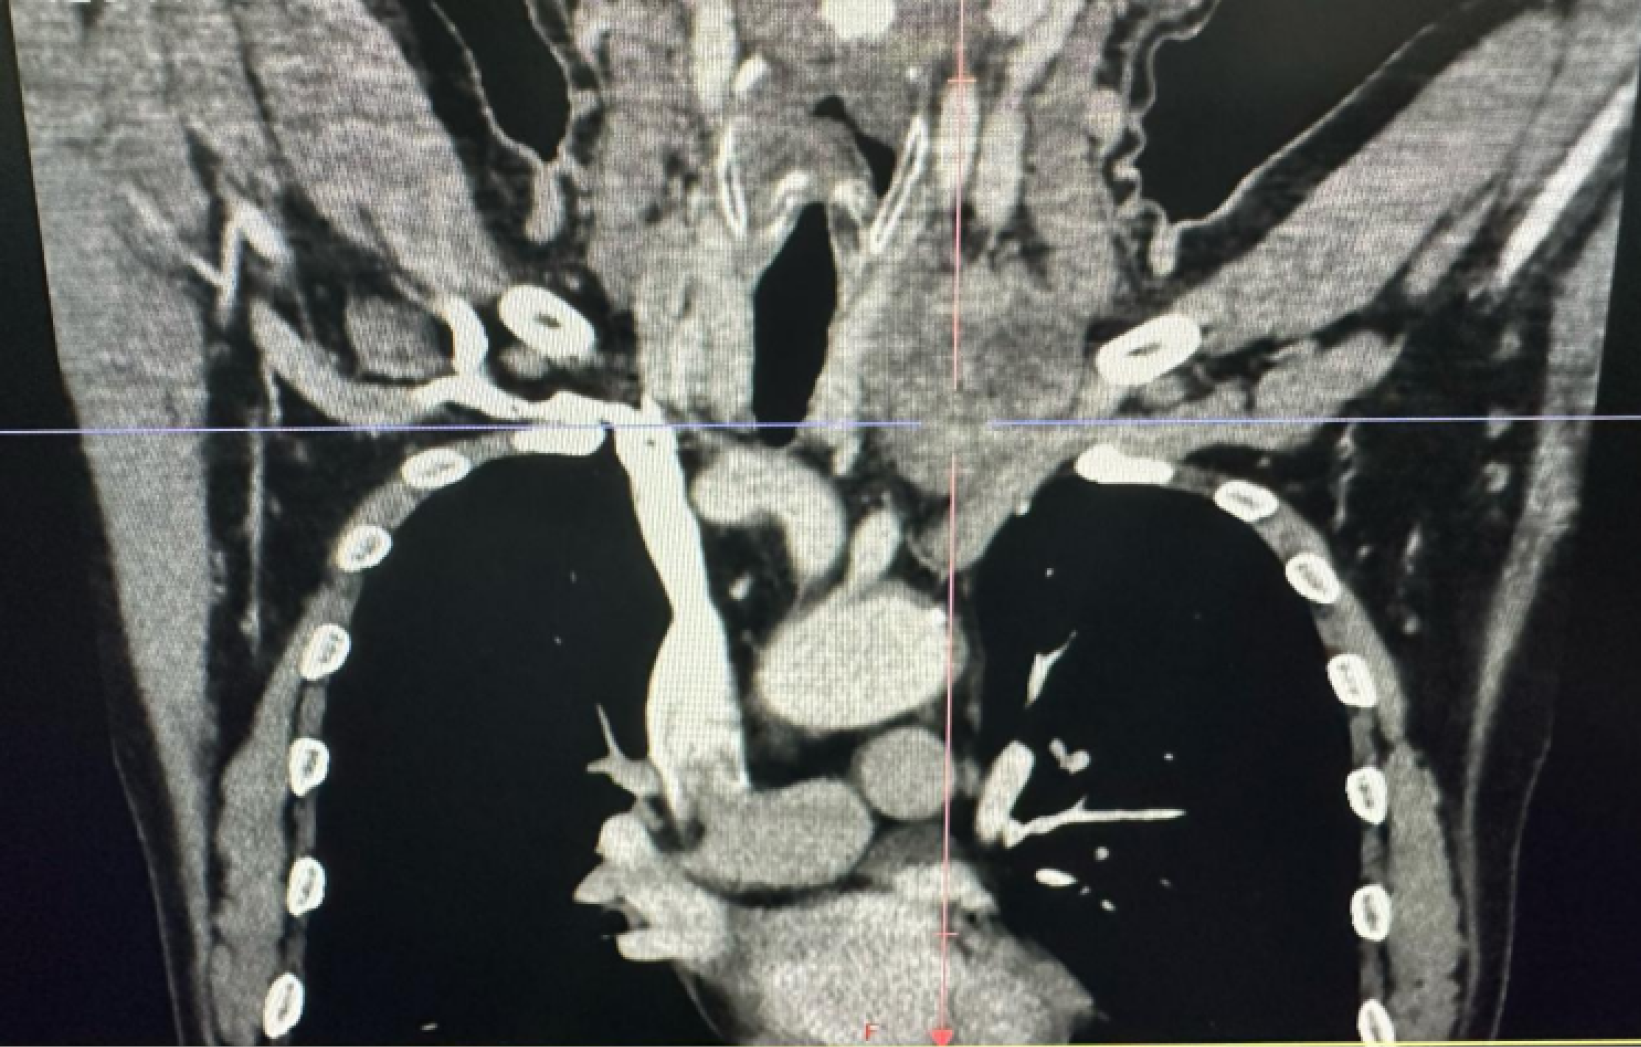

CT angiography/CT venography of head and neck vasculature: The lower portion of the left internal jugular vein was encased by the thyroid mass, with unclear visibility and local truncation. Collateral circulation was observed around the mass. The right internal jugular vein showed no abnormalities (Figure 3). A fiberoptic laryngoscopy revealed left vocal cord immobility, left vocal cord edema, and congestion with poor vocal cord closure.

Preoperative imaging modalities, including ultrasound, CT, and CT angiography (CTA)/CT venography (CTV), provided our team with comprehensive vascular invasion assessment, enabling meticulous preoperative planning. This evaluation allowed anticipation of potential vascular reconstruction requirements, even accounting for scenarios where vascular repair might prove technically unachievable. Concurrently, preoperative assessment indicated the common carotid artery was relatively intact, with full preservation anticipated; otherwise, artificial arterial anastomosis would be necessary. Corresponding contingency plans and preoperative consultations were established accordingly. Dikici et al[8] thinks that invasion of IJV (internal jugular vein) with hypervascular tumor thrombosis is an extremely rare condition in PTC. Thrombosis of IJV is probably underdiagnosed. Early-stage diagnosis is important for long-term survival rates.